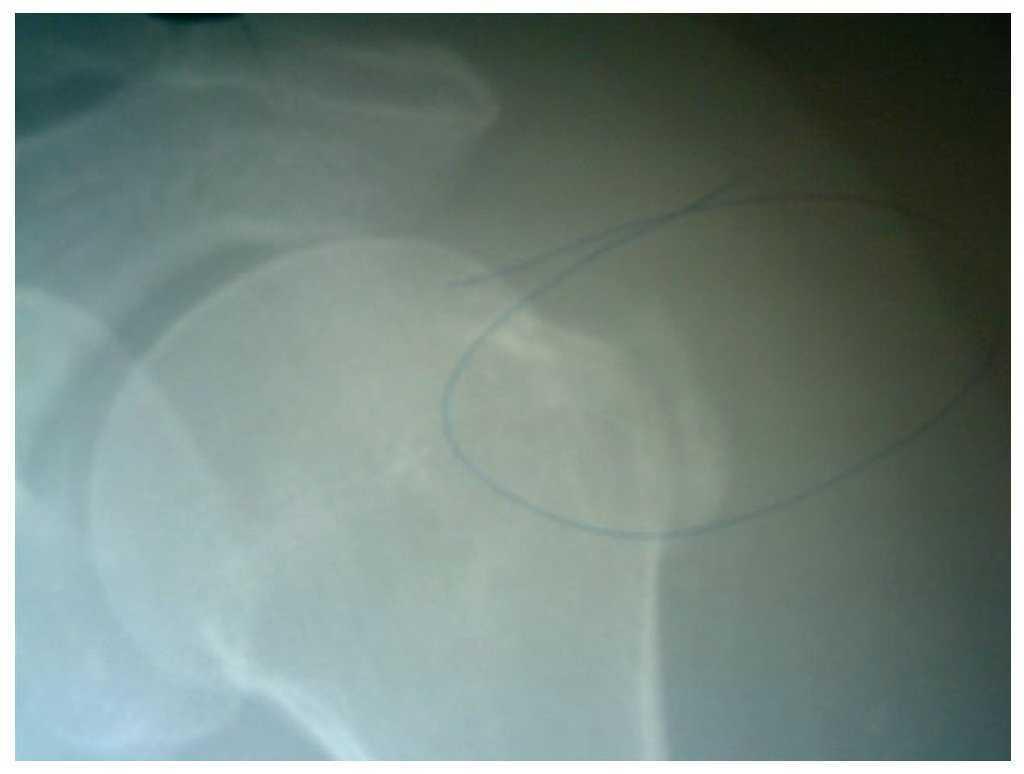

Aunque hay escasos trabajos publicados en la literatura universal acerca de este tema, los resultados obtenidos en este estudio son superiores a los encontrados por Fortin19, donde plantea que de 135 pacientes tratados con tendinitis calcificante se obtuvo una modificación de los depósitos de calcio del 55%, mientras que en nuestra investigación obtuvimos una curación del 73,9%, que representa los pacientes con alivio del dolor y resolución de la calcificación en más del 80% del tamaño inicial (figs. 5 y 6).

Figura 5 Tendinitis calcificada de hombro antes del tratamiento láser.

Figura 6 Tendinitis calcificada de hombro después del tratamiento láser.